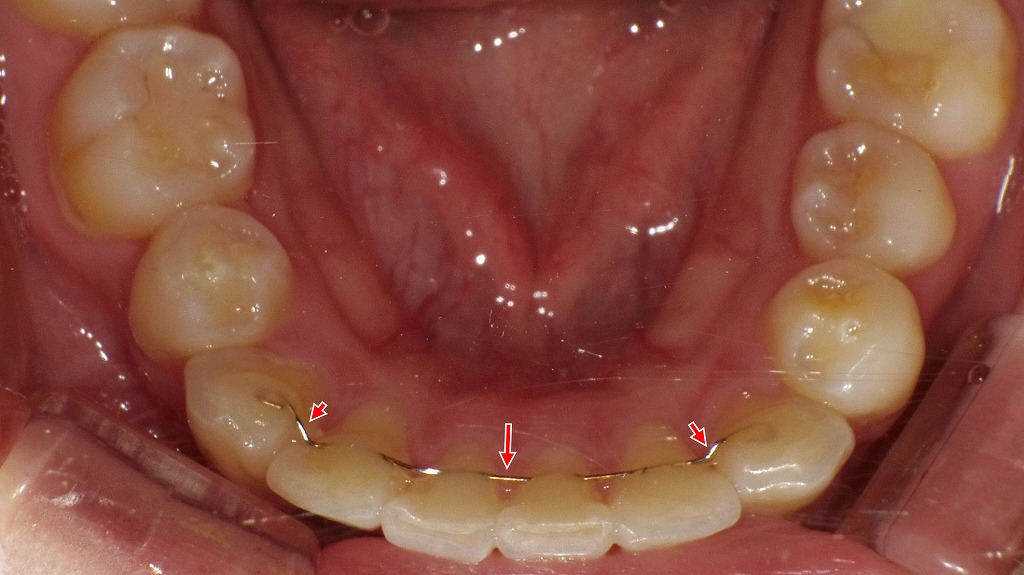

リテーナーには、取り外し可能な「マウスピース型」や、歯の裏側に接着する「固定式」などがあります。指示された期間、1日20時間以上の装着を守ることが、歯並びをキープする最も確実な方法です。